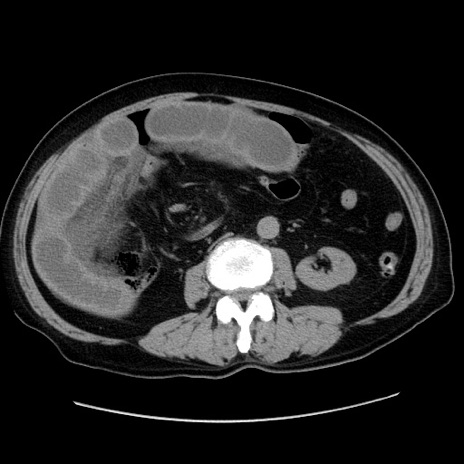

症例30(横断像)

【症例】80歳代男性

【主訴】臍周囲痛

【現病歴】約6時間前から臍下部痛が出現。次第に腹部膨隆・背部痛も生じてきたため来院。背部痛の場所は変化しない。

【既往歴】腎盂腎炎

【身体所見】意識清明、BT 36.3℃、BP  131/87mmHg、P 87bpm、SpO2 100%(RA)、臍周囲自発痛・圧痛あり、反跳痛なし、自発痛部位に一致して板状硬あり、腹部膨隆、腸雑音減弱、CVA tenderness両側陰性。

【データ】WBC 19600、CRP 0.33